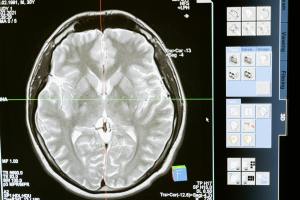

Start with the basics: brain scanning technology itself. fMRI and PET scans aren’t just research tools—they’re technologies that have fundamentally changed how we understand behaviour. Now add AI software interpreting those scans, potentially diagnosing conditions before human experts spot the patterns. Suddenly we’re discussing how technology doesn’t just study behaviour; it actively shapes our understanding of what behaviour even is.